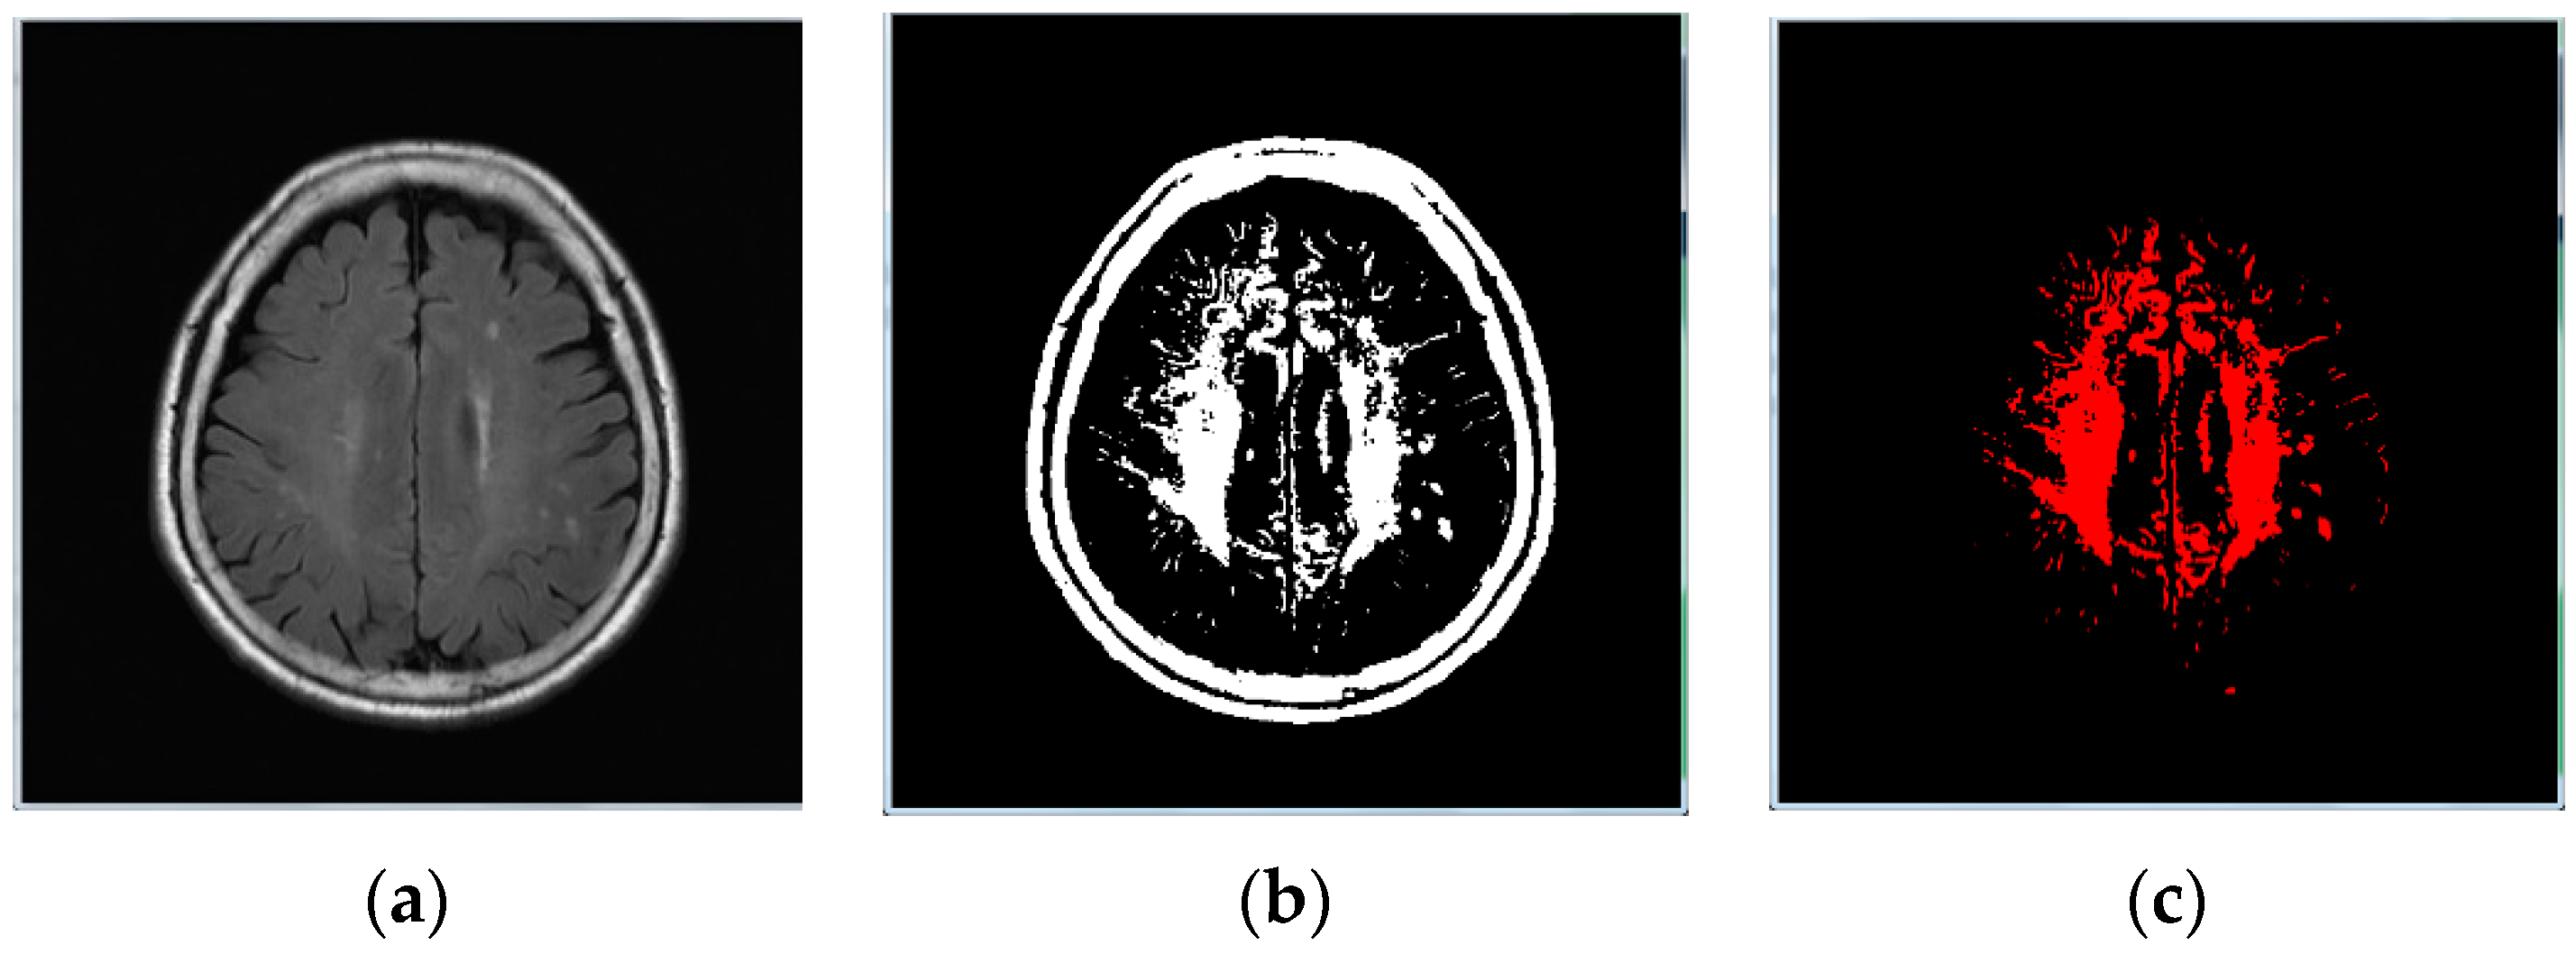

- Image binarization: We made sure the cranium (head shell) with the maximum region in image (Figure 1b);

- Image inverse binarization: The image from step 1 was adopted the inversed-binarization method in order to obtain the cerebrum region (Figure 1d,e);

- Identify the cerebrum region: The cerebrum region was obtained from step 3 and then compared with the region obtained by step 2. The union of the two step regions was calculated to identify the cerebrum region (Figure 1f);

- Perform median filtering to remove noise (Figure 1g); and

- Calculate the actual size and position of the brain (Figure 1h).